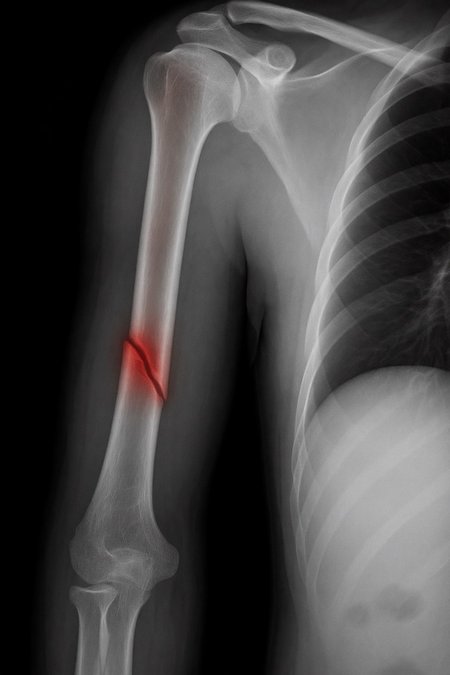

Can a model like Flux Kontext, designed for editing art and photography, be used to work with medical images, for example, with something 'as simple' as red-marking fractures?

The quick answer: it does do something interesting, but it over-scores and is far from reliable as a medical tool. It's a prototype to play with the idea, nothing more.

2. Ask: “Make marks where there is a fracture”.

Important

This LoRa is for visual experimentation only. It is not a medical device, it is not reliable and should not be used for clinical diagnosis.

Of course, taking into account that it is open source, fast (25 seconds per analysis) and that it can run on desktop computers, I think it is worth continuing to experiment with this concept in the future... we will see!